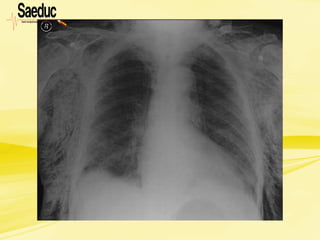

Hemotórax • Mecanismo detrauma: traumatismo torácico penetrante (mais comum) ou fechado. Quando suspeitar? na presença de: • Taquipnéia; • Dor torácica; • Respiração superficial; • MV ausente ou diminuído do lado afetado;

Hemotórax • 90% doscasos o tratamento é eficiente apenas com drenagem. • 10% é necessário intervenção cirúrgica, toracotomia ou laparotomia exploradora. • Pode apresentar -se normotenso ou hipertenso. • Quando hipertenso está associado a pneumotórax.

Hemotórax • Macicez àpercussão do hemitórax afetado; • Sinais clínicos de choque (cada espaço pleural pode reter até 2500 a 3000 ml de sangue,no adulto); • Confusão mental e ansiedade, dependendo da magnitude do comprometimento respiratório e cardiovascular; • Pensar na associação com pneumotórax, especialmente nos traumas penetrantes.

Hemotórax O sangue coletadona cavidade pleural tem 4 origens: • Parênquima pulmonar (90% dos casos); • Vasos sistêmicos (intercostais, mamários); • Lesões de mediastino (coração, vasos da base); • Ferimentos toraco-abdominais

Hemotórax Classificação • Pequeno: 300a 350 ml de sangue drenado • Médio: 350 a 1500 ml de sangue drenado • Grande: maior que 1500 ml